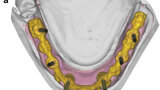

Fig. 12a: Occlusal view showing CAD of the final FDP (a) and detailed screenshot of the interface geometry (b).

Fig. 12b: Occlusal view showing CAD of the final FDP (a) and detailed screenshot of the interface geometry (b).